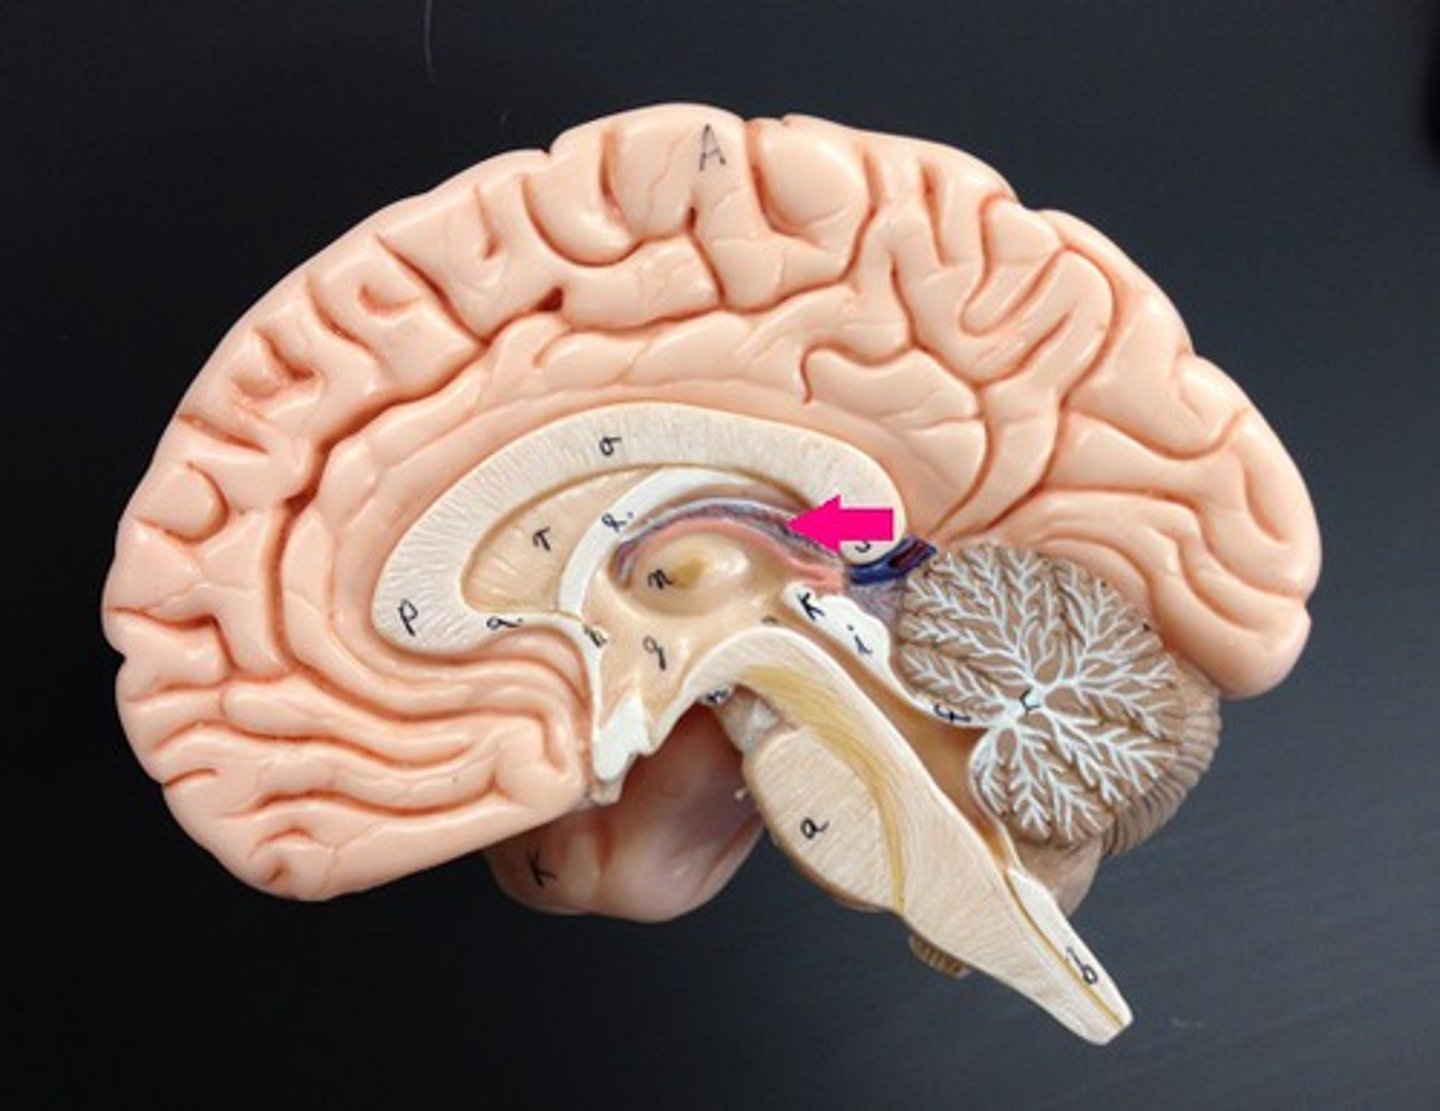

Diencephalon

made up of epithalamus, thalamus and hypothalamus

Thalamus

bilateral egg shaped nuclei connected by interthalamic adhesion and forming superior wall of 3rd ventricle. relay station for info coming from cortex.

Hypothalamus

forms floor of 3rd ventricle , cap over brain dtem and 3rd ventricle. Visceral control center, 3 fs

Pineal Gland

a pea-sized conical mass of tissue behind the third ventricle of the brain, secreting a hormone like substance in some mammals.

Infundibulum

the hollow stalk that connects the hypothalamus and the posterior pituitary gland.

Pituitary Gland

the major endocrine gland. A pea-sized body attached to the base of the brain, the pituitary is important in controlling growth and development and the functioning of the other endocrine glands.

Optic Chiasma

the X-shaped structure formed at the point below the brain where the two optic nerves cross over each other

choroid plexus

network of capillaries in ventricle walls

cerebral aqueduct

connects 3rd and 4th ventricle